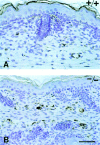

Thrombospondin (TSP) 2, and its close relative TSP1, are extracellular proteins whose functions are complex, poorly understood, and controversial. In an attempt to determine the function of TSP2, we disrupted the Thbs2 gene by homologous recombination in embryonic stem cells, and generated TSP2-null mice by blastocyst injection and appropriate breeding of mutant animals. Thbs2-/- mice were produced with the expected Mendelian frequency, appeared overtly normal, and were fertile. However, on closer examination, these mice displayed a wide variety of abnormalities. Collagen fiber patterns in skin were disordered, and abnormally large fibrils with irregular contours were observed by electron microscopy in both skin and tendon. As a functional correlate of these findings, the skin was fragile and had reduced tensile strength, and the tail was unusually flexible. Mutant skin fibroblasts were defective in attachment to a substratum. An increase in total density and in cortical thickness of long bones was documented by histology and quantitative computer tomography. Mutant mice also manifested an abnormal bleeding time, and histologic surveys of mouse tissues, stained with an antibody to von Willebrand factor, showed a significant increase in blood vessels. The basis for the unusual phenotype of the TSP2-null mouse could derive from the structural role that TSP2 might play in collagen fibrillogenesis in skin and tendon. However, it seems likely that some of the diverse manifestations of this genetic disorder result from the ability of TSP2 to modulate the cell surface properties of mesenchymal cells, and thus, to affect cell functions such as adhesion and migration.